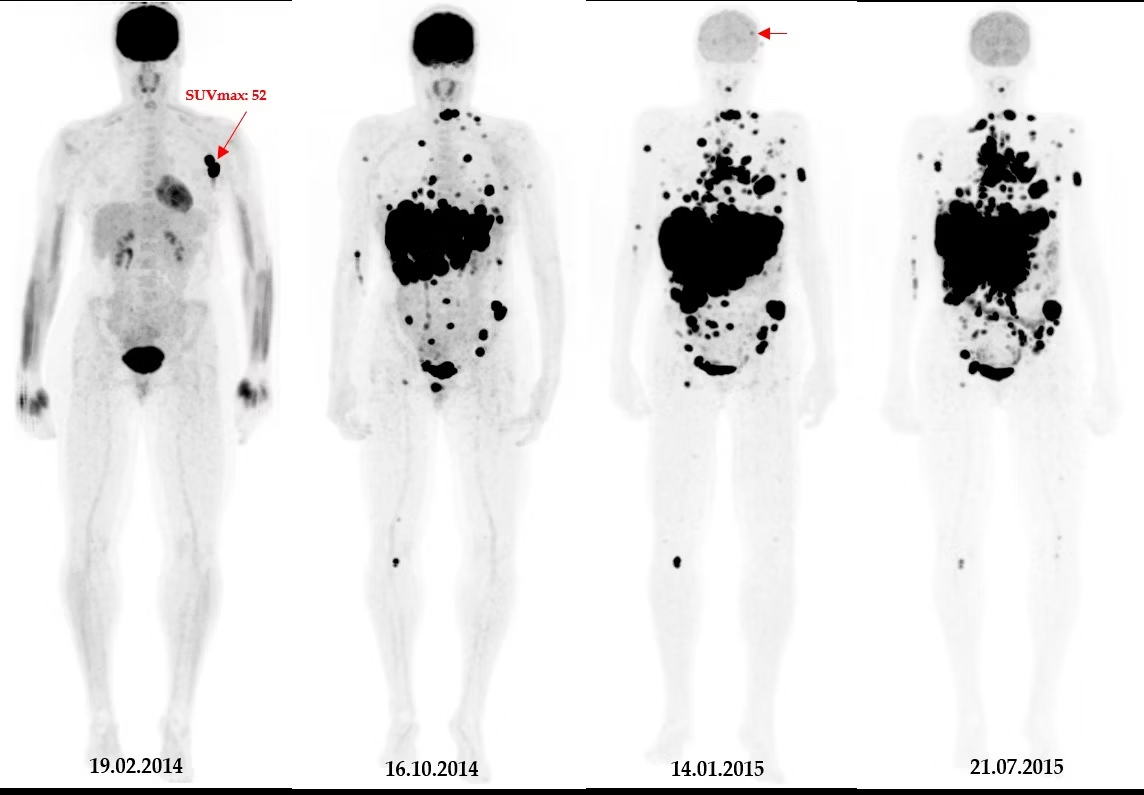

What is a scout?

A quick X-ray or CT that is scanned prior to the PET

It tells the system where we want the PET scanning to start and end – defines the parameters

What are the 4 types of PET acquisitions?

Limited area

Dynamic

Skull-base to mid-thigh

Whole body

What is the skull-base to mid-thigh acquisition?

Most common acquisition for PET imaging

We would start scanning the patient from their eyes → end at their thighs